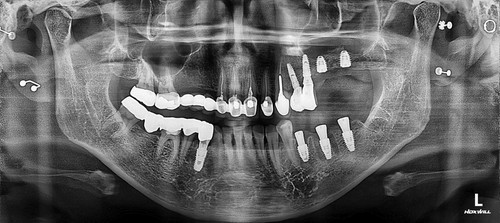

저희 치과에 오신 거는 발치한 날로부터 약 3주가 지난 상태로 오셨는데 발치한 치과에서는 한달이 안 되었기 때문에 더 기다려 볼 것을 권유 받으셨었습니다. 그런데 환자분이 제가 구강상악동누공에 대하여 작성한 포스팅을 보시고 저희 치과를 방문하시게 되었습니다. 보통 발치한지 3주가 되면 구강상악동천공의 단계를 지나서 구강상악동누공의 상태로 발전하게 됩니다. 내원 당시에 찍은 시티에서 10mm 이상의 천공이 확인 되었고 막아 놓았던 비흡수성 차례막을 제거하니 자연 치유될 정도의 천공이 아닌 걸로 확인하고 상악동누공폐쇄술을 시행하기로 하였습니다.

상악동누공폐쇄술이 성공하면 그 다음 단계로는 치조골 이식과 임플란트 식립을 해야 하는데 간혹가다 일반적인 상악동거상술에 비하면 누공이 있었던 부위는 상악동점막과 잇몸살이 유착되어서 힘든 경우가 많습니다. 물론 폐쇄술을 시행하면서 상악동에 뼈이식을 동시에 하는 것도 하나의 방법이 될수 있겠으나 성공했을 때 뿐만 아니라 누공폐쇄술이 실패했을 때를 가정한다면 통상적으로 동시 뼈이식을 시행하기에는 다소 위험성이 따르는 것이 사실입니다. 그래서 이 환자분은 안전하게 단계적으로 진행하기로 하였으며 누공폐쇄술이 성공한 후에 상악동 측방거상술을 시행하였고 이식한 뼈가 충분히 굳은 후에 임플란트를 식립하였습니다.

임플란트를 식립한 후에는 통상적으로는 3개월 후에 임플란트 보철물이 들어가는데 환자분의 사정으로 치과 내원을 못 하셔서 약 5개월 후에 오셨는데 왼쪽 아래 치아의 뿌리 부위의 충치가 발견되어서 아래 치아는 발치하면서 식립하는 즉시식립을 해 드렸습니다.

보통 하악에 임플란트 식립하면 2개월 이내에 치아가 들어가는데 마찬가지로 환자분 사정으로 못 오시다가 6개월이 지나서야 위,아래 임플란트 머리가 들어가고 마무리 할수 있었습니다.